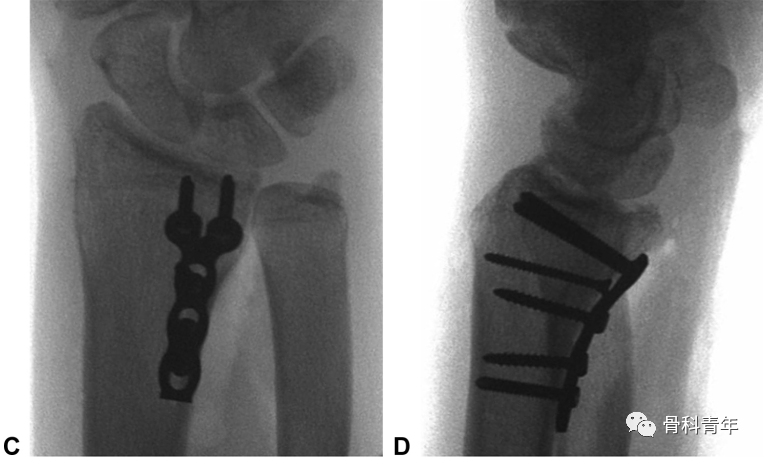

病例2:采用常规桡侧腕屈肌入路,掌侧钢板固定,术后发现腕关节前脱位,内固定失效。

对病例2,采用掌尺侧入路,柱钢板翻修后提示内固定位置良好。

鉴于常规桡骨远端骨折钢板在固定该骨块上存在以下缺陷:一是采用桡侧腕屈肌入路,显露欠佳,二是掌侧锁定板螺钉大,对小骨块固定不确切,并可能将螺钉置入骨块间隙导致骨块移位。因此学者建议采用2.0mm或2.4mm锁定钢板特异性固定中柱骨块。此外,除支撑钢板外,采用2枚螺钉固定骨块后,中和钢板保护螺钉,也是一种内固定的可选方案。

该病例采用2枚螺钉固定骨块后,钢板置入保护螺钉。